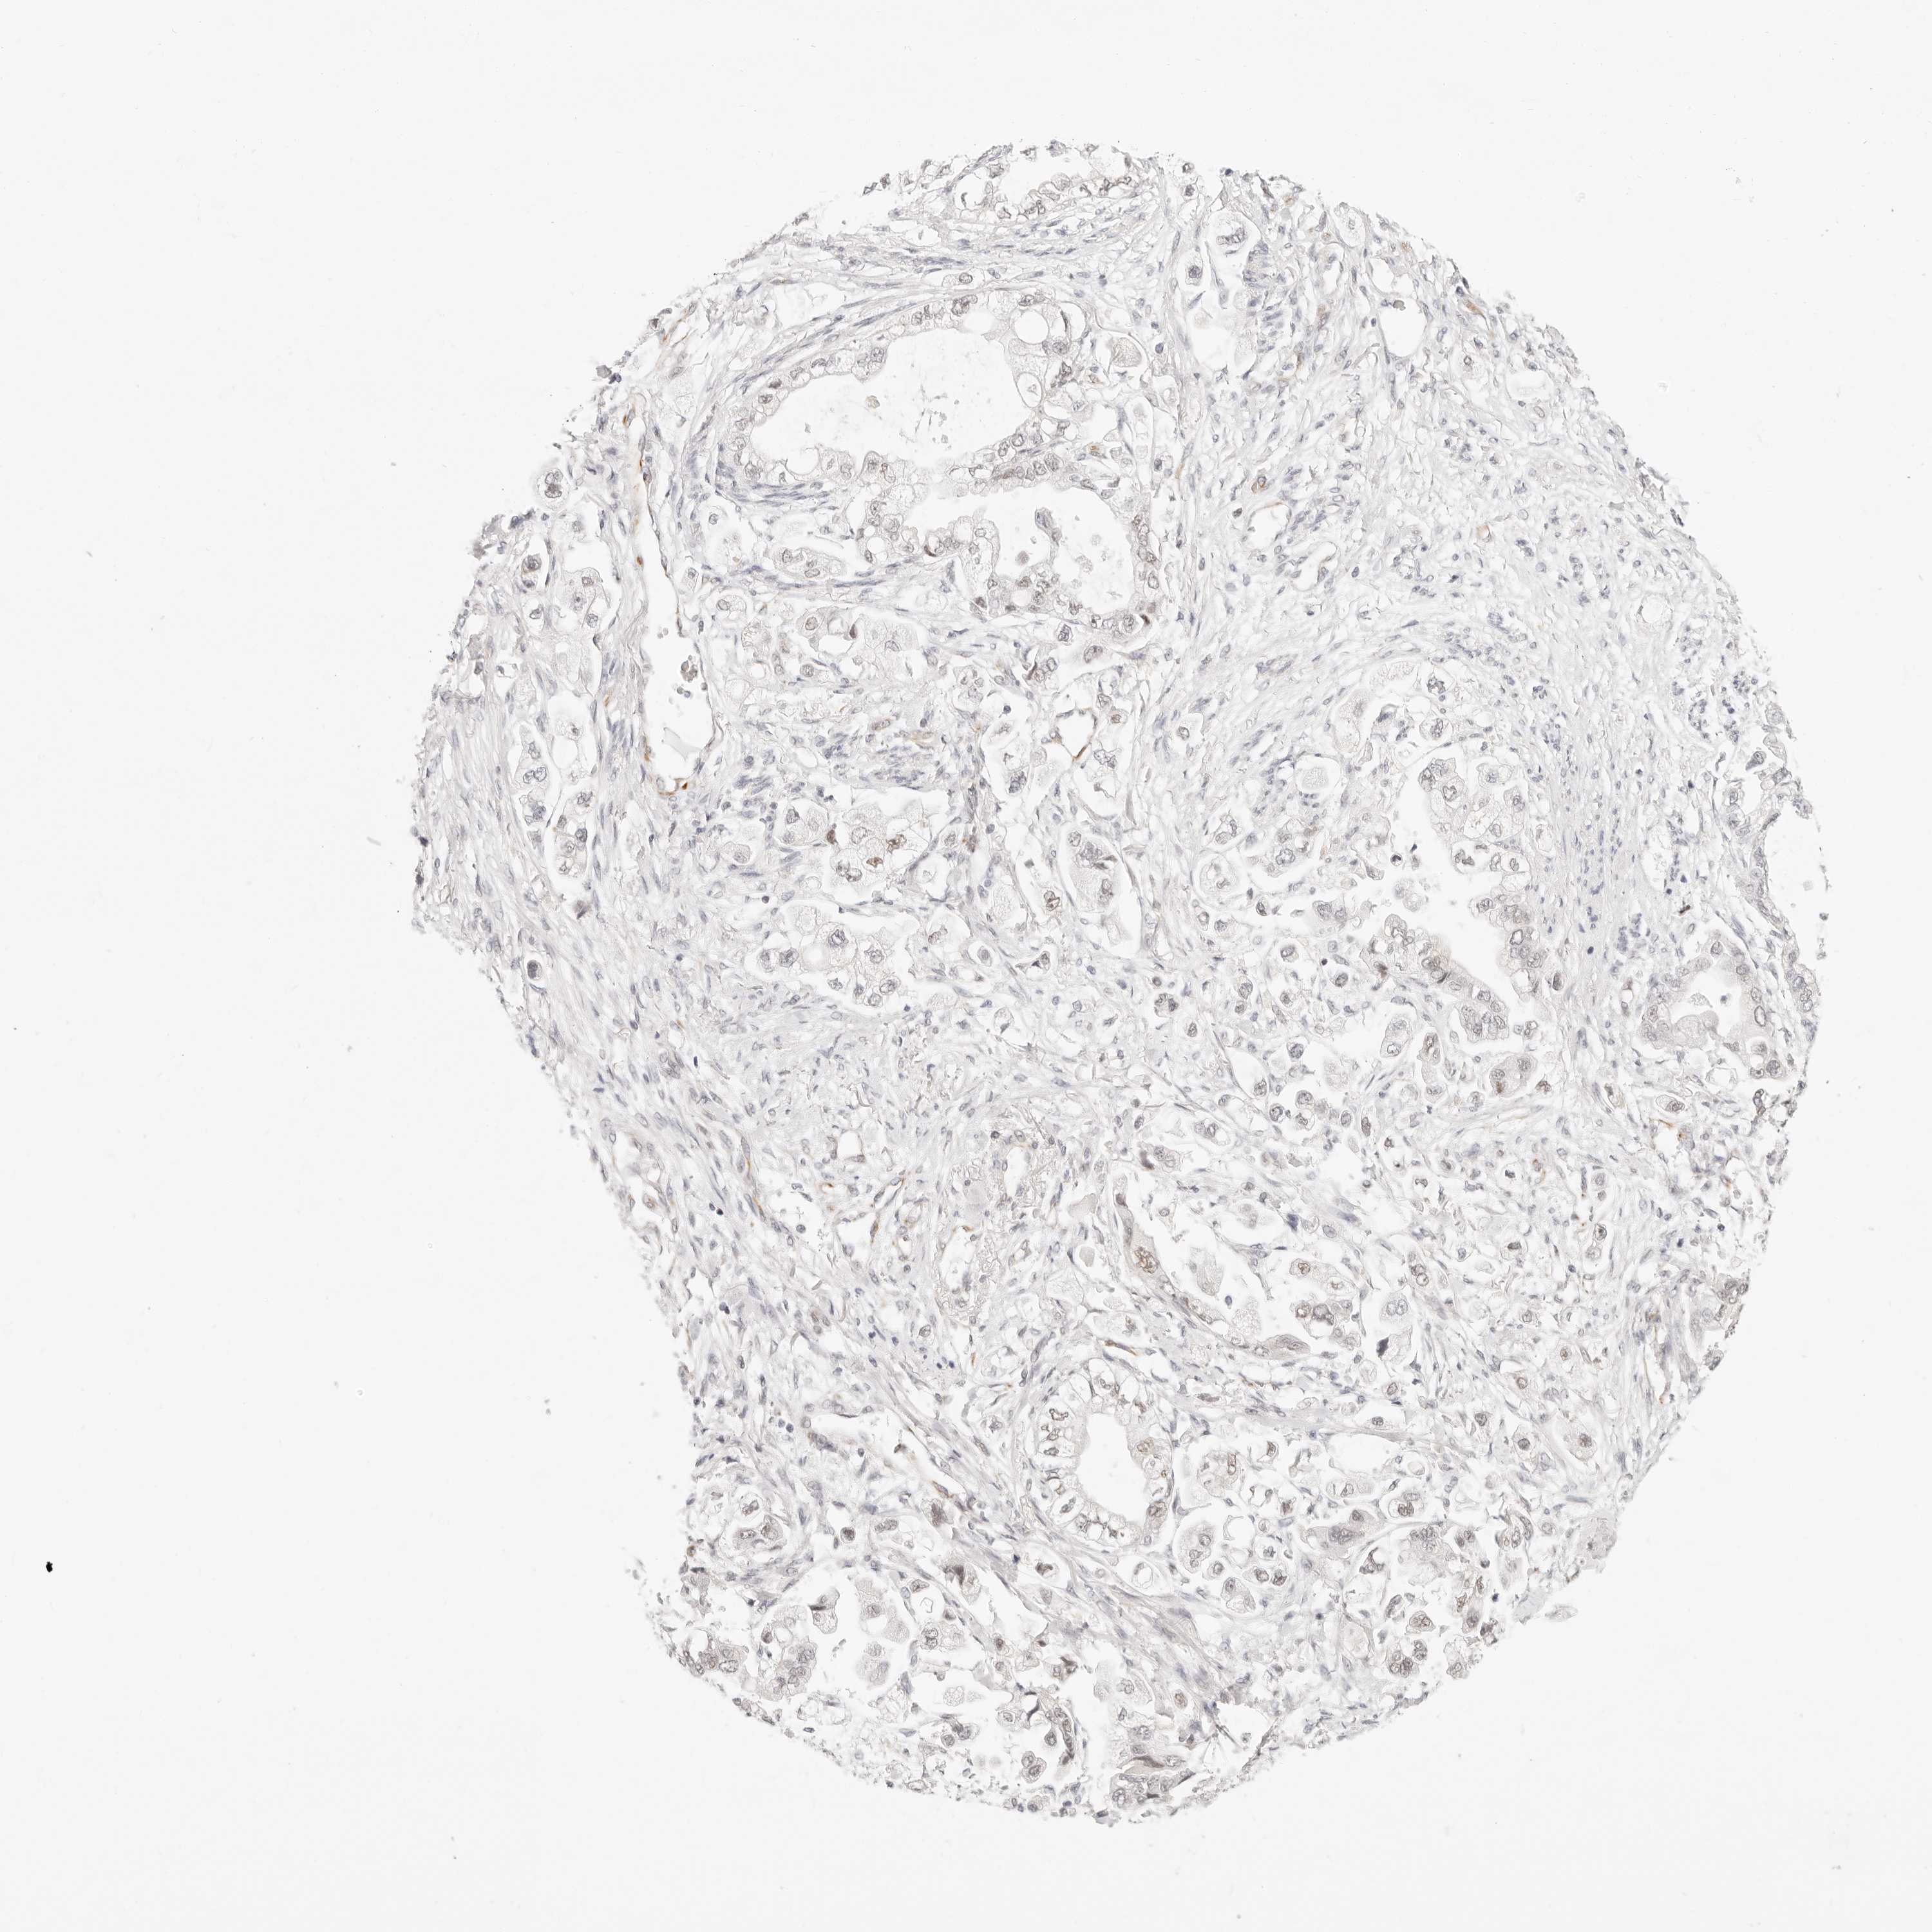

STOMACH CANCER - Protein expressioni

A mouse-over function shows sample information and annotation data. Click on an image to view it in a full screen mode. Samples can be filtered based on level of antibody staining by selecting one or several of the following categories: high, medium, low and not detected. The assay and annotation is described here.

Note that samples used for immunohistochemistry by the Human Protein Atlas do not correspond to samples in the TCGA dataset.

Antibody stainingi

Antibody staining in the annotated cell types in the current human tissue is reported as not detected, low, medium, or high, based on conventional immunohistochemistry profiling in selected tissues. This score is based on the combination of the staining intensity and fraction of stained cells.

Each image is clickable and will lead to virtual microscopy that enables deeper exploration of all samples and also displays staining intensity scores, fraction scores and subcellular localization as well as patient and tissue information for each sample.

Antibody HPA026439

Antibody HPA028490

Antibody HPA028526

Staining

High

Medium

Low

Not detected

Intensity

Strong

Moderate

Weak

Negative

Quantity

>75%

75%-25%

<25%

None

Location

Nuclear

Cytoplasmic/membranous

Cytoplasmic/membranous,nuclear

Adenocarcinoma, NOS